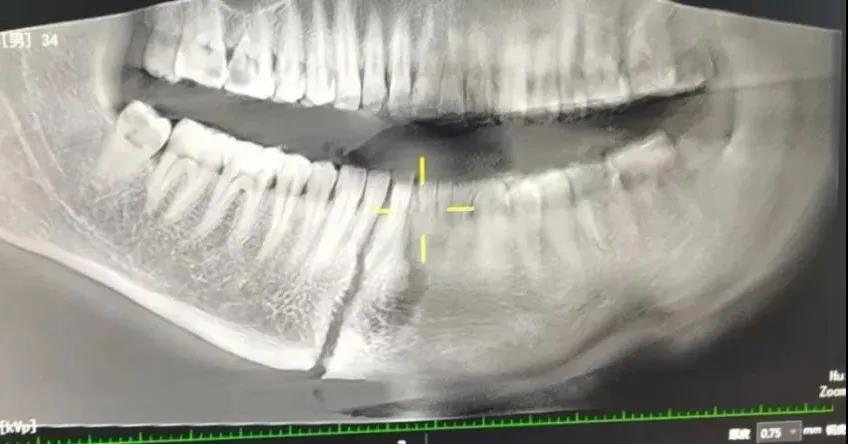

34岁的小麦因锯木头时不慎受伤,家人第一时间将其送到了疏勒县人民医院,此时患者不能张嘴,身体活动障碍。接诊医生立即安排患者做下颌骨CT及口腔CBCT检查,诊断为:开放性下颌骨多发性骨折及舌体多处撕裂伤。山东援疆专家刘峰主任仔细为患者查体,询问病史,立即通知消毒供应室、手麻科做好术前准备工作。

刘峰主任介绍,“当时考虑到患者下颌骨骨折为开放性且舌体多处裂伤,情况非常复杂。为了治疗过程有效推进,早日解除患者痛苦,口腔科手术团队立即组织开展了详细的疑难病例讨论,决定急诊行开放性下颌骨多发性骨折复位内固定术+ 舌体多处撕裂伤清创缝合术+颌间牵引固定术。力求通过一次手术修复多处骨折,避免患者多次手术而受到更多创伤。”

经过科室医疗团队的讨论以及家属的同意后,手术在全麻下进行,援疆专家刘峰主任亲自主刀实施手术,在吾拉木江·努尔吉力主任,阿布都赛米江医师,沙吉旦医师的全力配合下行舌体清创,逐层缝合,在从下颌刻部伤口内进行下颌体骨折复位,用钛板钛钉进行内固定,再用钛钉口内牙龈处进行颌间牵引固定。手术进行得十分顺利,患者恢复非常理想。